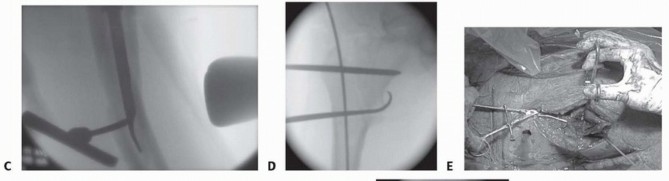

** Fracture Reduction Reduction of the fracture is tantamount to success. My preferred technique for the proximal femur involves a four-step technique. After attachment to the foot positioner or skeletal traction with the perineal post attached, posterior sag is corrected at the fracture with a force directed from posterior to anterior and maintained. The leg is flexed through the foot holder 20 to 30 degrees from neutral for intertrochanteric personality fractures and 30 to 40 degrees for subtrochanteric personality fractures, maintaining the posterior to anterior reduction force at the hip ( TECH FIG 1A). Traction is applied to restore length in line with the body. No varus. The leg is rotated to align with the proximal fragment, 5 to 15 degrees of external rotation for most subtrochanteric personality fractures and intertrochanteric personality fractures may be externally rotated 10 degrees or placed in 15 degrees of internal rotation for as the variability of femoral neck anteversion is larger than previously recognized. 5

TECH FIG 1 • A. Reduction maneuver with force directed posterior to anterior at the fracture to align anterior cortices, flexion of distal fragment to match proximal fragment, and then longitudinal traction. B. Percutaneous Schanz pin as joystick in proximal fragment.

(continued)

Acceptable alignment is confirmed with the C-arm in both views. The surgeon ensures there is adequate room in the pelvic and abdominal areas for the insertion of the wires, reamers, and implants in relation to the fracture table. A 3 L bag of saline may elevate the pelvis high enough to allow room for the instrumentation. The reduction can then be fine-tuned with intramedullary instruments or by percutaneous joysticks or pushers ( TECH FIG 1B,C). If the reduction is not acceptable at this point, the surgeon should stop and reevaluate the position of the C-arm and the amount of traction (too little or too much). The surgeon should not start reaming the proximal femur until reduction control is demonstrated. If reduction cannot be obtained by joysticks and percutaneous bone hooks ( TECH FIG 1D), the surgeon should proceed to open reduction using the lower portion of a Watson-Jones-type approach to the hip (TECH FIG 1E-I). The surgeon should avoid dissecting the medial soft tissue envelope, where the vascularity is located. A single cerclage wire will be most helpful if there is a coronal split of the proximal fragment. Use of multiple cables or wires is avoided. The clamps and reduction tools are maintained as the implant is inserted. 393